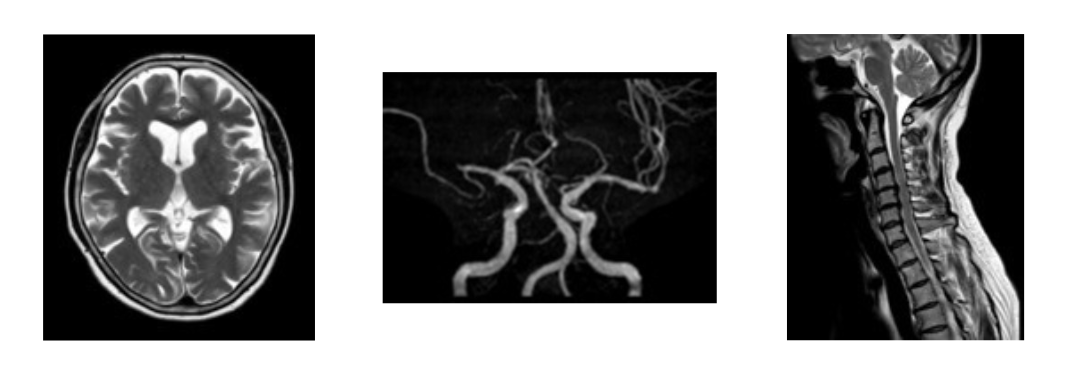

【脳】 【脳血管】 【頸椎】